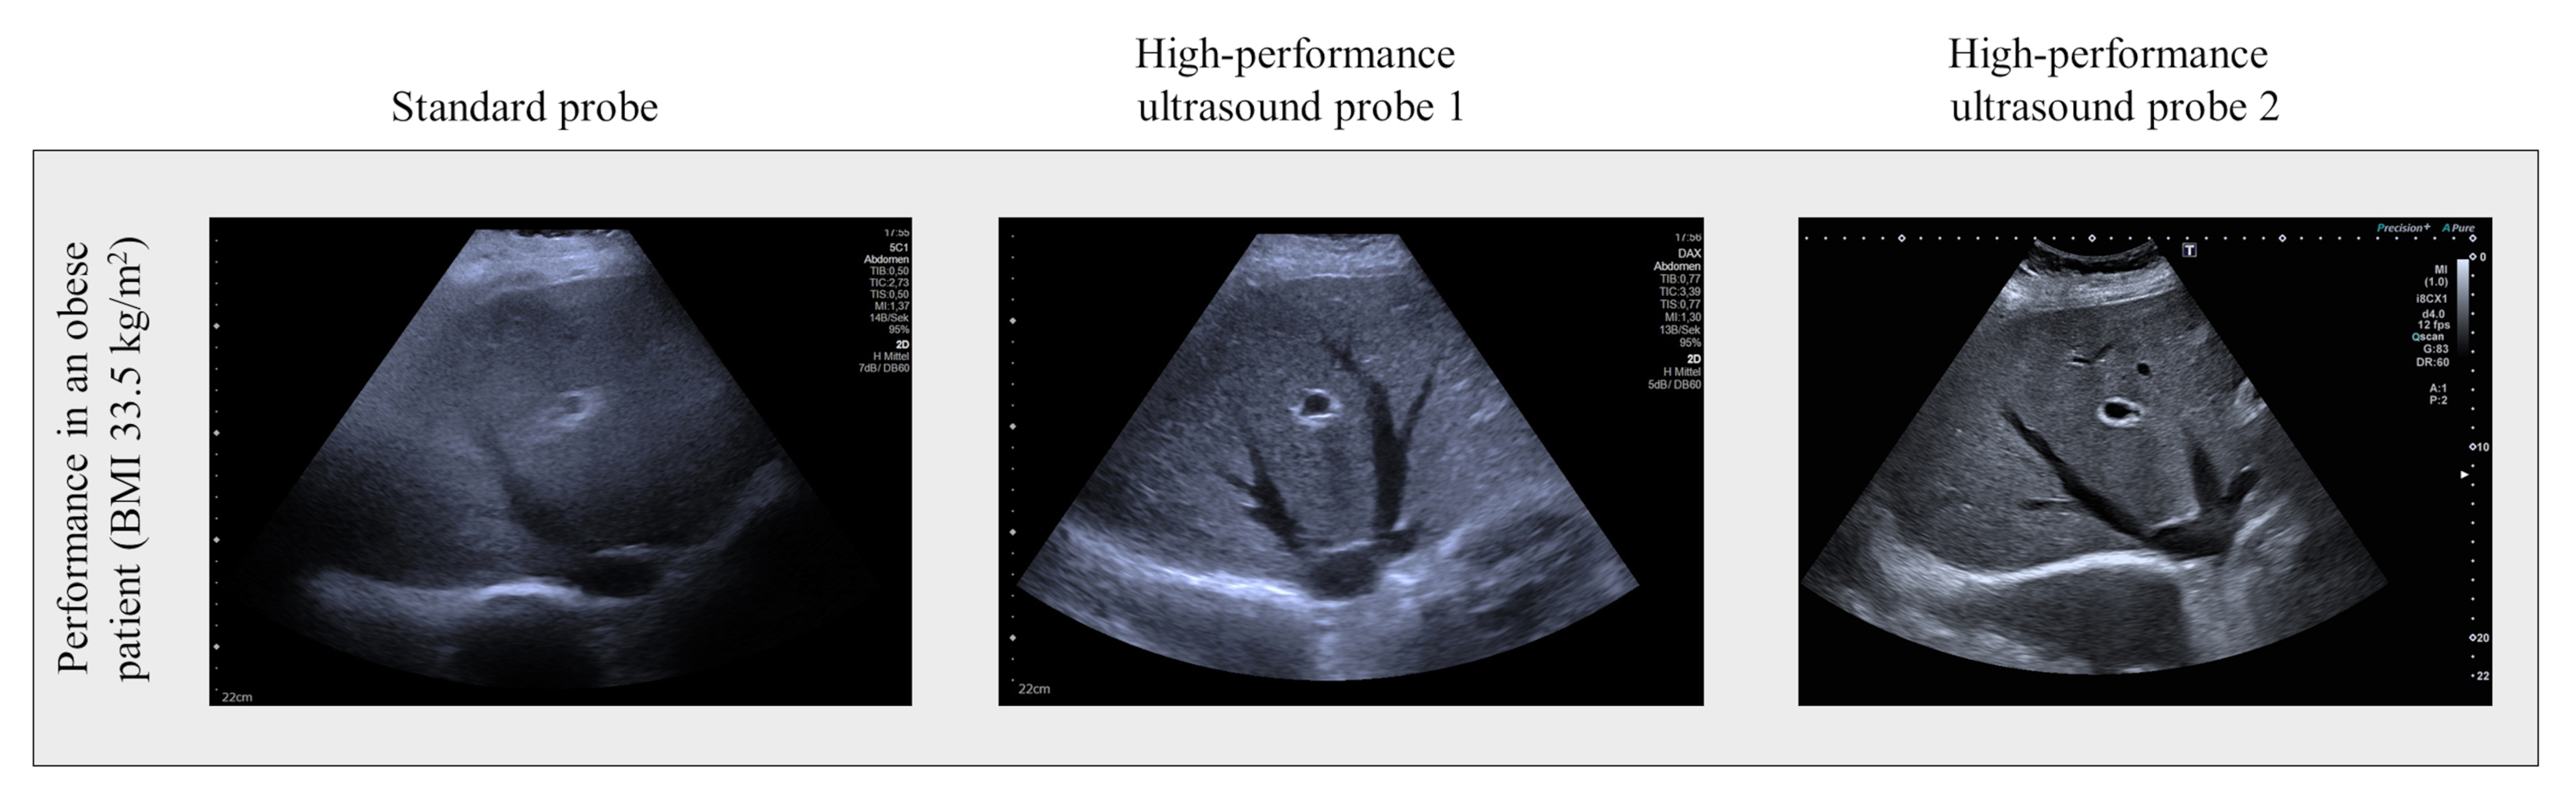

The current data show that these relatively expensive special probes for ultrasound equipment can provide significant added value. The 40 participants in the study underwent a highly standardised ultrasound examination of the abdomen with three different probes: a standard probe and two high-performance probes. The liver and right kidney were examined in people with varying degrees of obesity, and the quality of the ultrasound imaging was scored.

In a recent clinical study at the University of Leipzig Medical Center, researchers found that the quality of ultrasound scans of the liver and kidneys was significantly lower in obese patients. “The results showed that as the body mass index of the patients increased, the image quality of the ultrasound decreased. It also became clear that modern probes with matrix technology improve the quality of ultrasound imaging,” says Professor Thomas Karlas, head of the study and corresponding author of the current publication. The matrix probes have an improved transmitting and receiving performance and therefore achieve greater penetration depth into the tissue. This allows for better diagnostic accuracy in high-risk patients. The performance of matrix probes in obese individuals has not yet been scientifically validated.